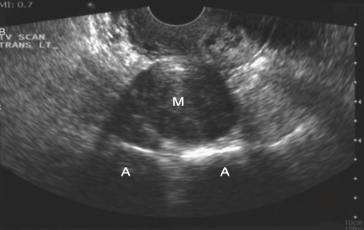

Identify the echogenicity

Isoechoic